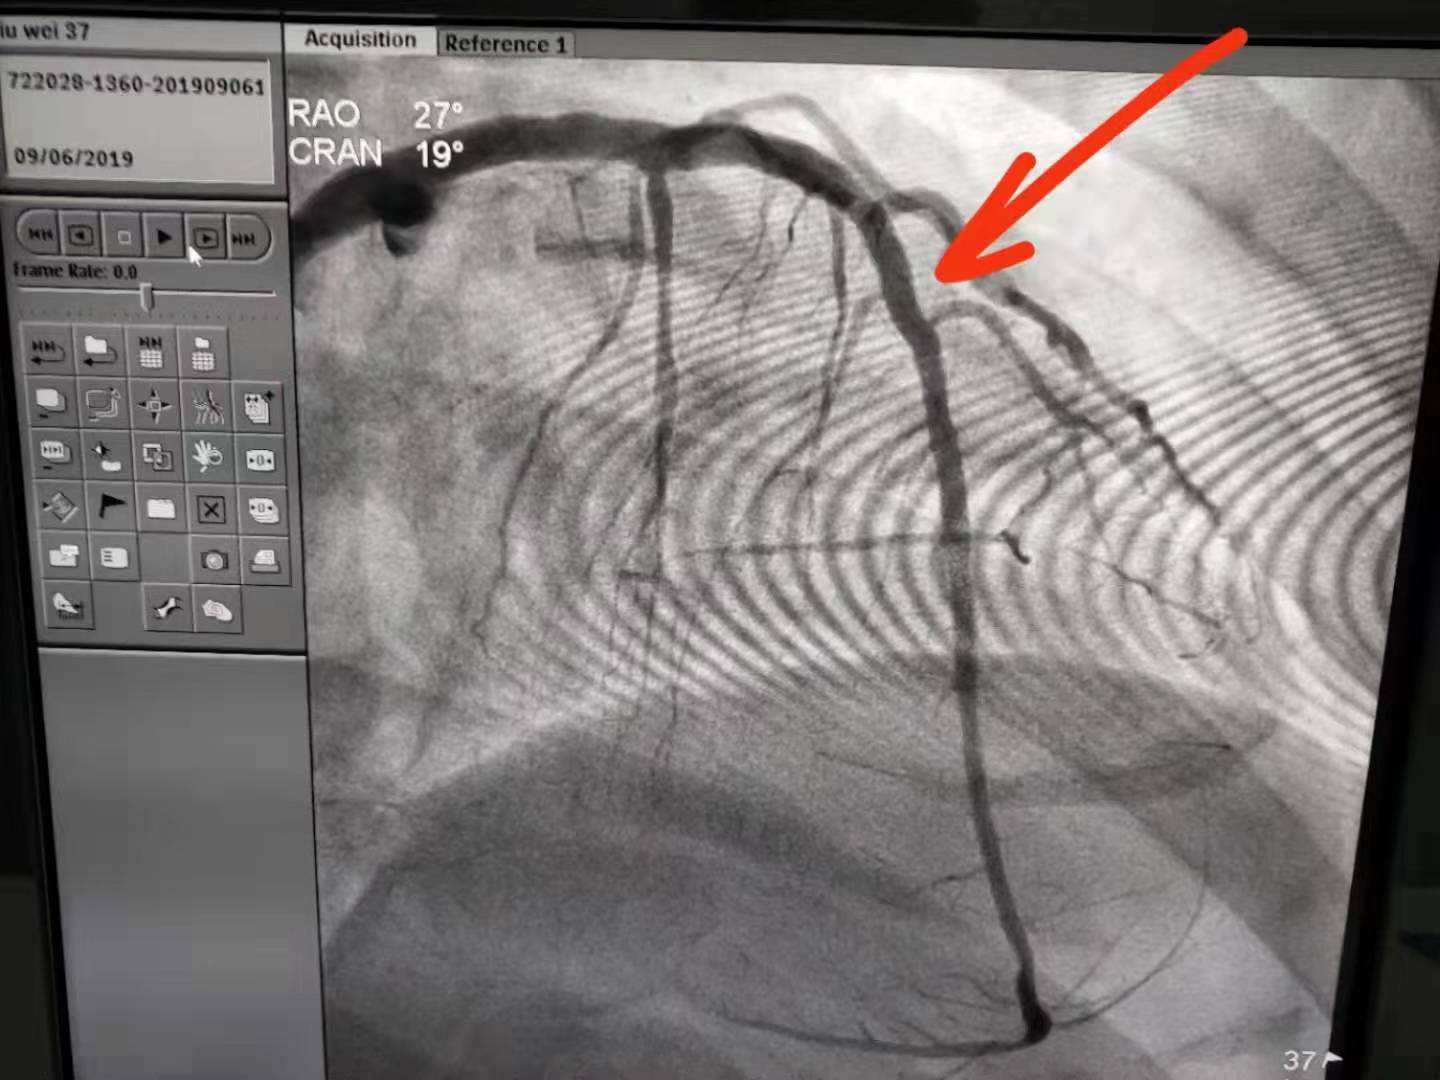

近日,一位患者突发心前区不适伴心慌,市人民医院急诊科医护人员迅速出诊,心电图提示急性下壁ST段抬高型心肌梗死,立即口服“心梗一包药”并监测生命体征,启动胸痛绿色通道,行急诊冠脉造影术,发现右冠状动脉闭塞,开通了梗死的靶血管,植入1枚支架,患者转危为安,术后恢复良好。

急性心肌梗死(AMI)是冠状动脉血流中断或减少,导致相应心肌细胞缺血坏死,是目前影响人类健康以及致死、致残的主要疾病之一。随着经济发展及生活方式改变,我国AMI的发生率持续增长。早期、快速地再灌注治疗是改善AMI患者预后的关键。而介入治疗因其微创、并发症少,血管开通率高等特点成为治疗急性心肌梗死的主要治疗手段。我院自开展急诊冠脉介入后不断优化流程,缩短患者血管开通时间,挽救濒死心肌,改善患者预后。